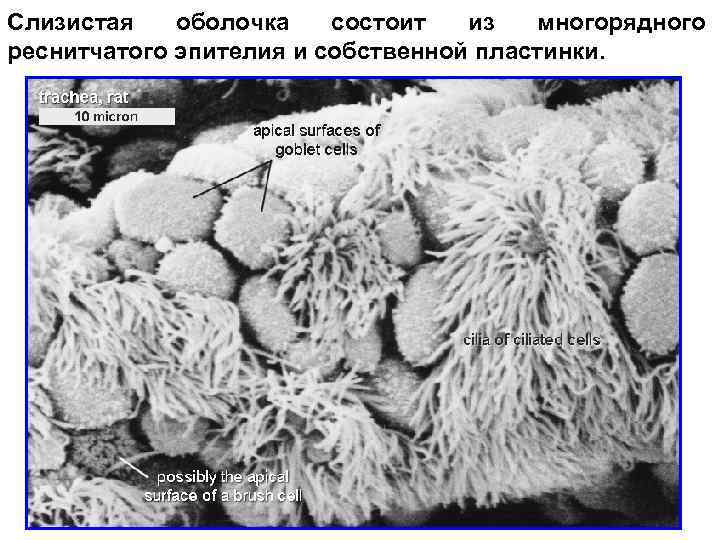

Слизистая оболочка состоит из многорядного реснитчатого эпителия и собственной пластинки.

Эпителий трахеи содержит реснитчатые, бокаловидные, вставочные и эндокринные клетки. Реснитчатые клетки имеют реснички, колеблющиеся против движения вдыхаемого воздуха. Они удаляют микроорганизмы и инородные частицы. Бокаловидные клетки секретируют муцины - слизь, которая склеивает инородные тела, бактерии и облегчает их выделение. Микроворсинчатые клетки являются хеморецепторными. Базальные или вставочные клетки играют роль камбия.